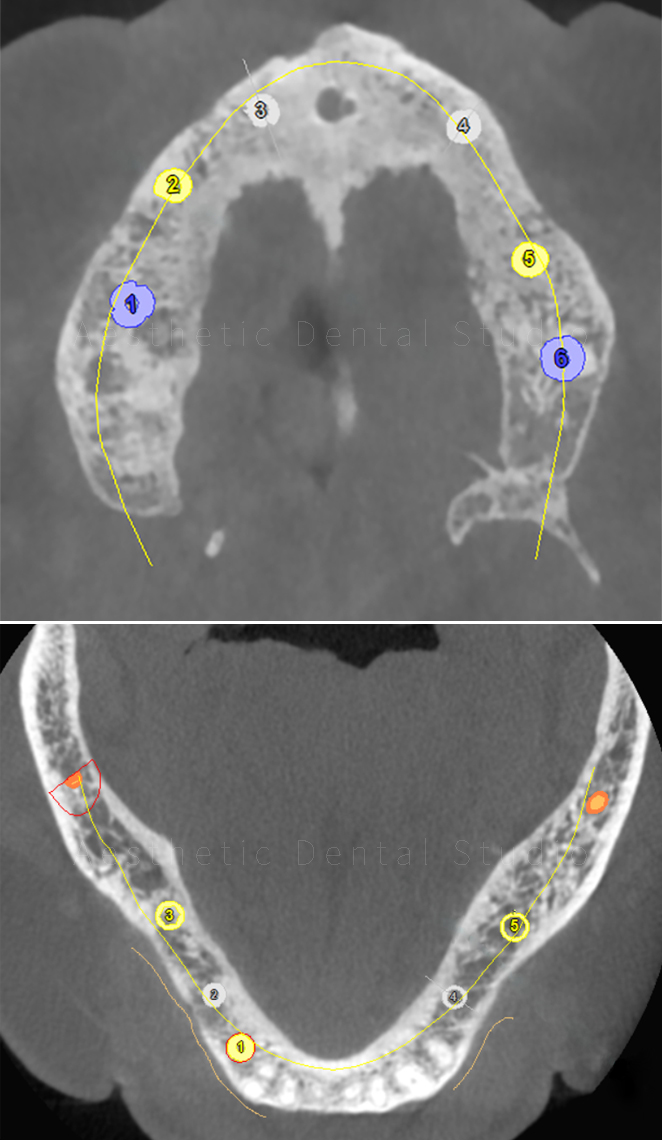

Με εξειδικευμένο οδοντιατρικό λογισμικό έγινε ψηφιακός σχεδιασμός και εικονική τοποθέτηση των εμφυτευμάτων, ώστε να εξασφαλιστεί απόλυτη ακρίβεια και ασφάλεια.

Ο σχεδιασμός στάλθηκε σε εξειδικευμένο κέντρο στη Γερμανία, όπου δημιουργήθηκε τρισδιάστατος χειρουργικός οδηγός, προσαρμοσμένος στο στόμα της ασθενούς.

Αυτός ο οδηγός χρησιμοποιήθηκε στο χειρουργείο για την τοποθέτηση συνολικά 11 εμφυτευμάτων με ακρίβεια χιλιοστού:

• 6 στην άνω γνάθο

• 3 στην κάτω δεξιά περιοχή

• 2 στην κάτω αριστερή περιοχή

Με αυτό τον τρόπο δημιουργήθηκε ένα σταθερό υπόστρωμα για την προσθετική αποκατάσταση ολόκληρου του στόματος.